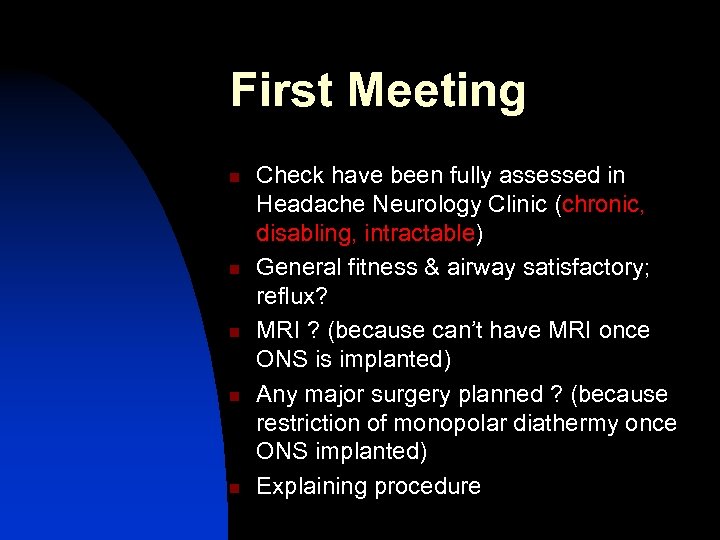

First Meeting n n n Check have been fully assessed in Headache Neurology Clinic (chronic, disabling, intractable) General fitness & airway satisfactory; reflux? MRI ? (because can’t have MRI once ONS is implanted) Any major surgery planned ? (because restriction of monopolar diathermy once ONS implanted) Explaining procedure